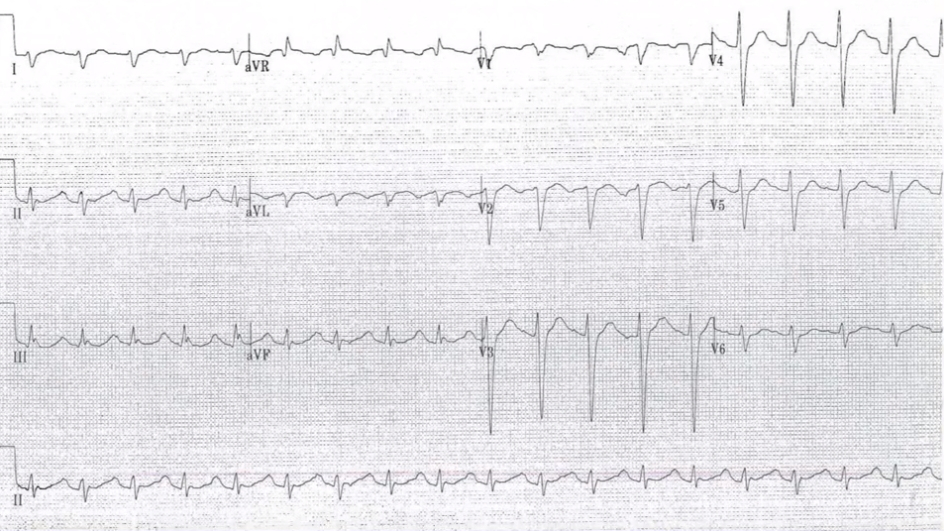

These are a series of electrocardiograms (ECGs) obtained from a patient with tricyclic antidepressant overdose. The first (above) shows the initial ECG demonstrating QRS interval prolongation and characteristic changes in AVR. The second (Severe cardiac toxicity) shows worsening changes consistent with progression of cardiac toxicity. Note the increases in the QRS interval and the R wave in AVR. The third (After treatment) shows narrowing of the QRS complex but persistent right axis deviation of the terminal 40 milliseconds following the initiation of treatment. The final ECG (Resolution) shows complete resolution of interval changes related to toxicity.

ECG with TCA poisoning: After treatment

ECG with TCA poisoning: Resolution